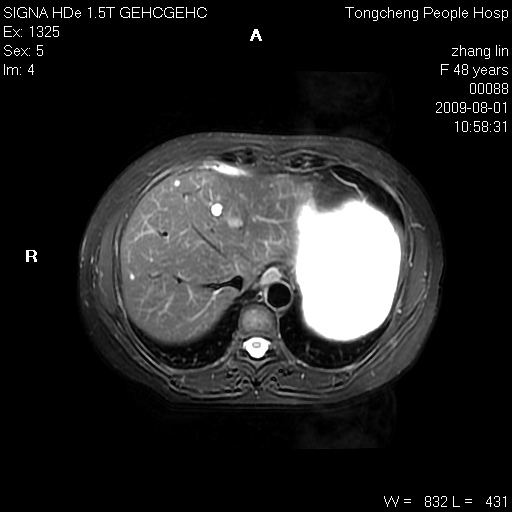

女,48岁。健康体检,彩超发现右肾占位性病变。平素健康。

临床诊断:右肾占位性病变,性质待定(囊肿?肿瘤?)。

上中腹部mr平扫+增强扫描,图像如下:

右肾上极见一类圆形病灶,t1wi呈等信号t2wi呈等高混杂信号,三期增强无强化,边界清---考虑囊肿出血。

同反相位均表现为等信号,病变无强化,考虑含蛋白的囊肿可能,弥散加权相或许有些帮助,

慢性胆囊炎